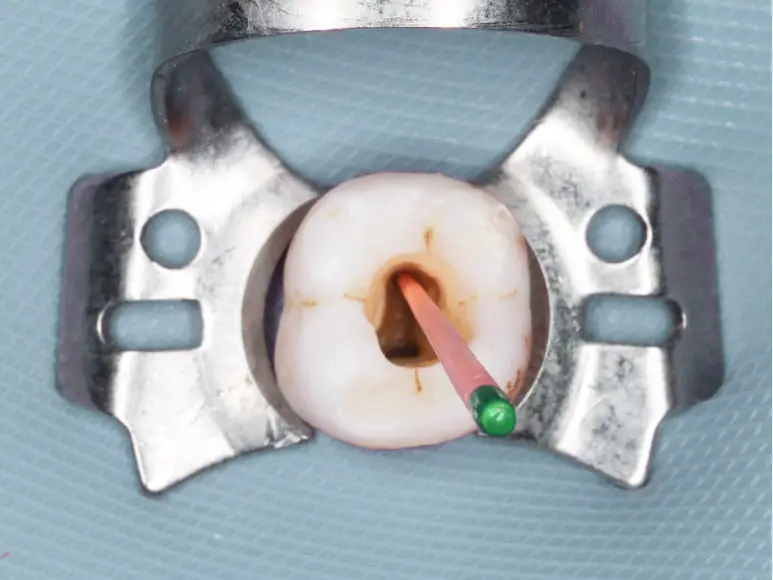

• 限りなく無菌に近い状態

限りなく無菌に近い状態

お口の中には、様々な細菌が存在します。

そのためラバーダムというバリアシートで歯を隔離し、唾液と一緒に細菌が流れ込むことを防ぎ、限りなく無菌に近い状態で治療を行います。

ラバーダムの準備

歯質がなくなったところから唾液が入らないように壁(隔壁)をつくり、ラバーダムがかけます。